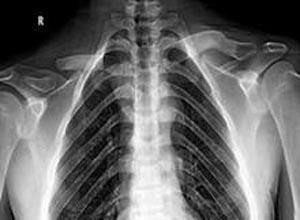

简介锁骨颅骨发育不全(cleidocranial dysostosis)综合征即Marie-Sainton综合征,又名Hulkerantt骨形成不全、Schenthaurer综合征等。颅锁发育不全的特点是膜内化骨部位的骨化不良,主要发生在锁骨、颅骨和骨盆。但软骨内化骨也会有些影响。病儿有轻度侏儒表现。